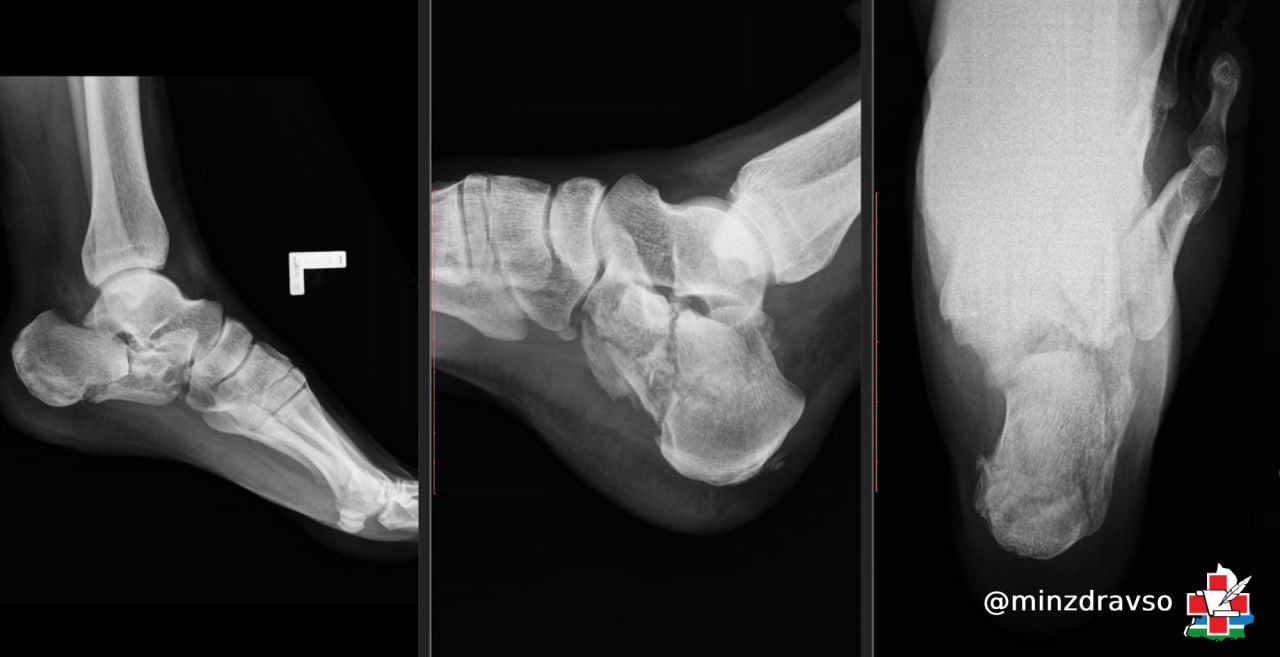

Режевлянин Дмитрий получил травму, упав в конце лета с лестницы высотой около трёх метров. Приземление было крайне неудачным — у мужчины диагностировали внутрисуставной оскольчатый перелом правой и левой пяточной костей. Травматологи Центральной городской клинической больницы №24 Екатеринбурга выполнили операцию по закрытому остеосинтезу спицами, что позволило восстановить целостность костей без осложнений. После этого мультидисциплинарной команде Областной специализированной больницы медицинской реабилитации «Липовка» предстояло помочь уральцу заново встать на ноги.